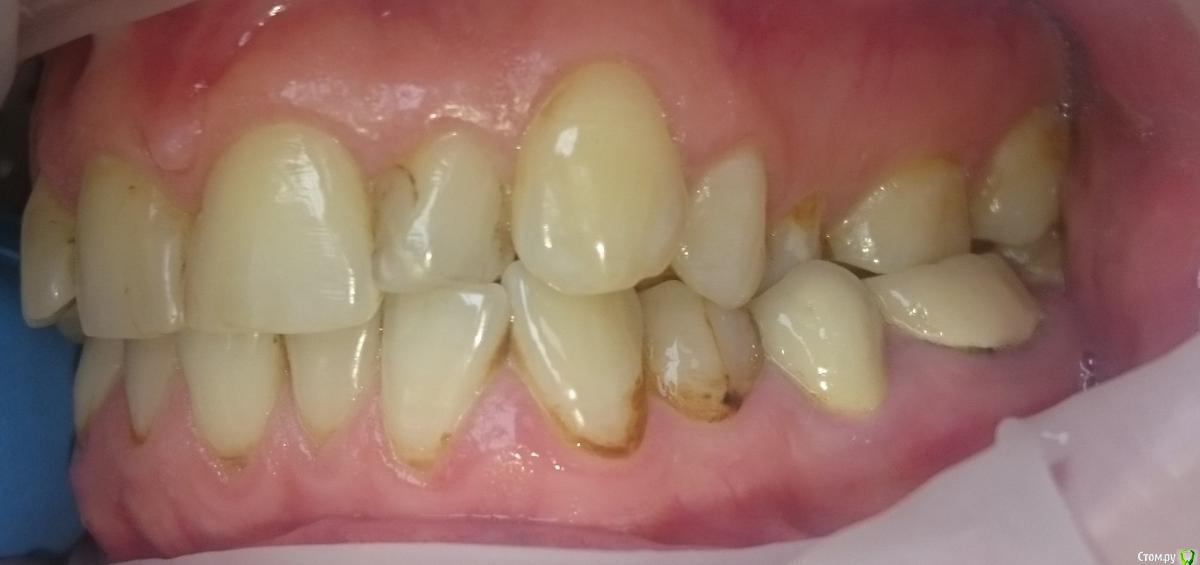

Metanira Опубликовано 17 апреля, 2015 Поделиться Опубликовано 17 апреля, 2015 Добрый день, дорогие стоматологи!Прилагаю снимок, сделанный в апреле этого года и фотографии. После него вылечена 4.4, так как вывалилась пломба. Очень хочу узнать ваше мнение по следующим вопросам и буду очень благодарна за любые ответы, не обязательно на все вопросы)Какие зубы стоит начать лечить в первую очередь? У меня очень много пломб, но менять их все не хочется, так как скоро от зубов ничего не останется( Пока планирую вылечить 2.1. В клинике к лечению посоветовали зубы: 14, 16, 17, 25, 26, 27, 34 (оверлей), 46 (оверлей), 47 (оверлей). С чего начать? Стоит ли пломбировать пришеечный кариес на нижних зубах? Врач рекомедовал лечить все зубы с 33 по 43. Они никак не беспокоят, боюсь лечить, так как боюсь, что появится чувствительность. Стоит ли пользоваться в моем случае монопучковой щеткой? Она у меня есть, но мне кажется, она все-таки жестковата. Что-то странное у меня с пломбой на 44-45 зубах сверху, она одна на 2 зуба, это как-то оправдано?) Какая щетка Cura Prox по вашему мнению лучше 5460 (один стоматолог сказал, что лучше ее использовать, так как чем мягче, тем лучше) или же 3960 (другой стоматолог посоветовал мне именно ее из-за сильного налета, после нее зубы кажутся белее, но боюсь, что для эмали она менее безопасна, чем 5460). Я курю и пью чай, зубы чищу регулярно, но вот такой вот налет. У меня щелкает правый сустав челюсти, стоит ли использовать Аква Сплинт или что-нибудь подобное ночью?Брекеты носить не планирую, так как мои зубы и эмаль этого точно не переживут.Заранее всех благодарю! Ссылка на комментарий

krokomot Опубликовано 17 апреля, 2015 Поделиться Опубликовано 17 апреля, 2015 Спасибо за ответ. Ошиблась, 2.2 как раз и хочу сделать в первую очередь. Эстетически меня вообще не беспокоит пришеечный кариес, поэтому если не стоит его трогать, то и не буду. Просто, как вы поняли, мне чуть ли не каждый зуб пломбировать или перепломбировывать, поэтому и хочу узнать, действительно ли все это необходимо или что-то можно не трогать. Ну и вопросы вроде довольно конкретные.... 1 решить сложно, что первее, не видя ситуации во рту, по ОПТГ ничего критичного не видно, там где в зубах пломбированы каналы стоит зделать прицельные снимки на придмет отсутствия околокорневой патологии. Так что думаю очередность на ваш выбор2. надо смотреть по ситуации если поврхностное поражение можно обойтись сошлифовыванием и полировкой затем минерализующая терапия и чувствительность, если она появиться - пройдет. А если процесс не поверхностный нужно реставрировать. Смысла в монопучковой щетке не вижу. Должна быть щетка средней жесткости, паста со фтором, правильная техника чистки зубов, зубная нить и ирригатор тогда с гигиеной проблем не будет, но надо делать профессиональную гигиену 2 раза в год.3. Пломб на 2 зуба быть не должно. И ответьте почему вы решили, что она на 2 зуба?4.Ответил в пункт 25. Шина возможно несколько улучшит ваше состояние, но проблемы с прикусом не решит, так что потихоньку готовтесь к иправлению прикуса. Ссылка на комментарий